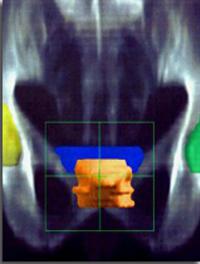

AFU – Paris. Dans le cancer de la prostate, la curiethérapie par implants d’iode 125 est réservée aux formes cliniques de pronostic [...]